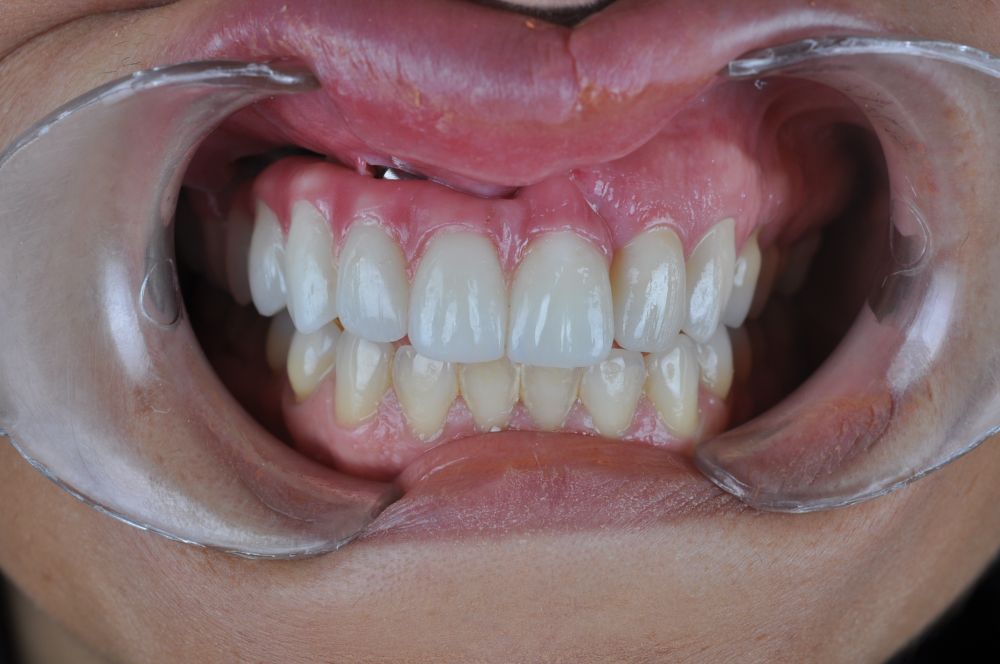

El día de la colocación de las estructuras, se arenó el interior de las coronas dentosoportadas con óxido de aluminio de 50 m y fueron cementadas con cemento de resina Multilink Ò. El puente implantosoportado se atornilló al torque indicado (20Nw) (Figuras 14, 15, 16 y 17).

La evolución postoperatoria fue favorable, sin complicaciones quirúrgicas. La paciente mostró una correcta cicatrización de los tejidos blandos tras la resección quirúrgica. A los 30 días de la cirugía, se inició el tratamiento con radioterapia adyuvante, completando un total de 30 sesiones sin incidencias relevantes.

Finalizado el tratamiento oncológico y confirmada la ausencia de enfermedad activa, se procedió a la segunda fase quirúrgica con la colocación de pilares transepiteliales Multiunit®. La integración de los implantes cigomáticos y del implante endoóseo fue satisfactoria, observándose estabilidad clínica y ausencia de signos de periimplantitis.

Las impresiones analógicas y el posterior flujo digital permitieron una correcta planificación protésica. Las estructuras definitivas, confeccionadas en óxido de zirconio monolítico sobre interfases metálicas de titanio, mostraron una adecuada adaptación pasiva tanto clínica como radiográficamente. La prueba estética permitió ajustes oclusales y funcionales mínimos, optimizando el resultado final.

En enero de 2021, el puente implantosoportado fue atornillado con un torque controlado (20 Nw), y las coronas dentosoportadas cementadas con éxito. La paciente refirió una notable mejoría en la función masticatoria, fonación y estética facial, manifestando un alto grado de satisfacción.

En el seguimiento a 4 años tras la colocación de la prótesis definitiva, no se observaron complicaciones mecánicas ni biológicas. La paciente continúa libre de enfermedad y con una correcta adaptación al tratamiento rehabilitador implantosoportado (Figura 18).